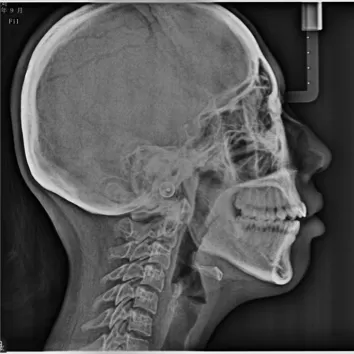

Rayons X avant le traitement

[Radiographie panoramique/Céphalogramme latéral]